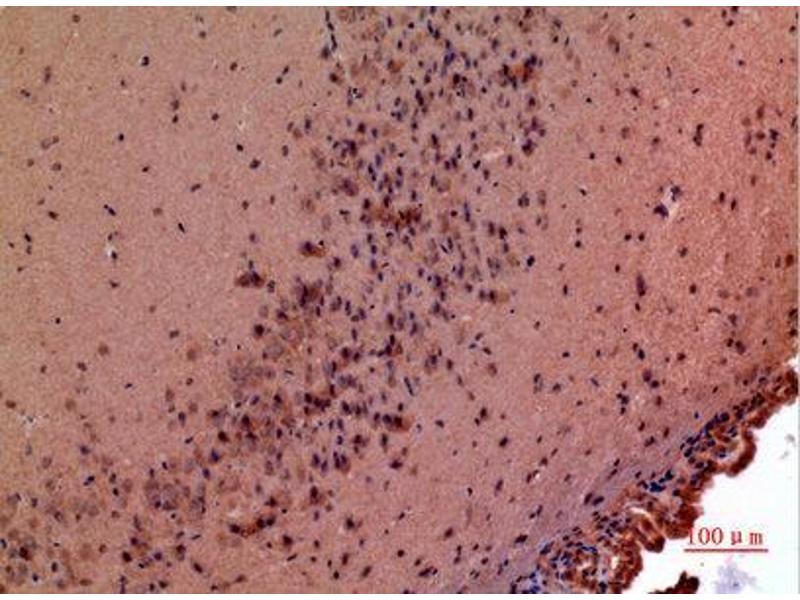

- WB 1:500-1:2000, IHC-P 1:100-1:300, ELISA 1:20000,